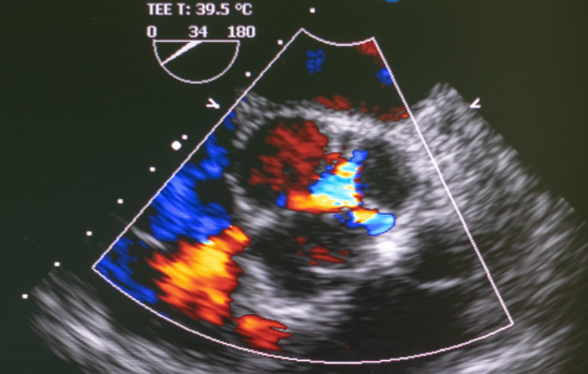

Cette première journée a pour objectif d’affiner vos compétences en analyse et en interprétation d’images à travers différents cas cliniques.

• Repérer, décrire et mesurer les lésions échographiques rencontrées

• Interpréter les anomalies afin d’établir un diagnostic différentiel

Ces deux journées de formation vous permettront d’affiner votre œil diagnostique et de reconnaître une plus large variété d’images physiologiques et pathologiques avancées. À l’issue de la formation, vous aurez consolidé votre pratique en échocardiographie et serez en mesure de prendre en charge des cas plus complexes avec davantage d’assurance et d’expertise.